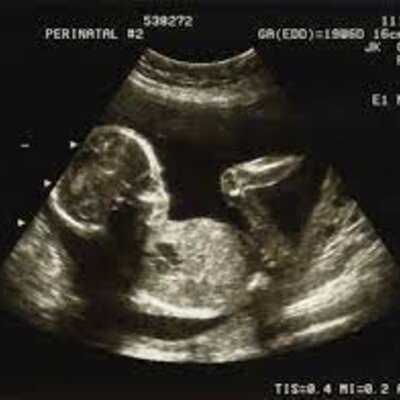

Stages of pregnancy- Mother